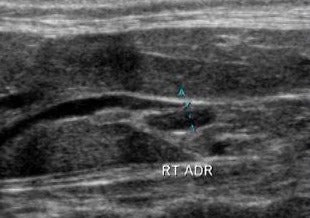

Cette session vous aidera à optimiser votre imagerie de petits mammifères exotiques. Nous discuterons de l'interprétation et des variations anatomiques. Une série de cas sera utilisée pour démontrer les anomalies et les présentations cliniques pour vous aider dans la pratique.

Exotique / Radiologie

Présenté par NatalieAntinoff DVM, DABVP (Avian)